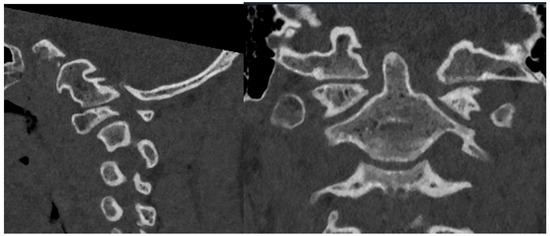

3.1. Preoperative Planning and 3DPI Design

3.2. Surgical Approach